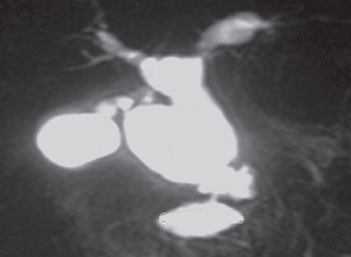

Q12. A 17-year-old presents with recurrent abdominal pain for 3 months. Amylase and lipase are raised. What is the likely diagnosis based on USG and MRCP findings?

- Choledochal Cyst

- Annular Pancreas

- Pancreas Divisum

- CBD stone

Answer – A